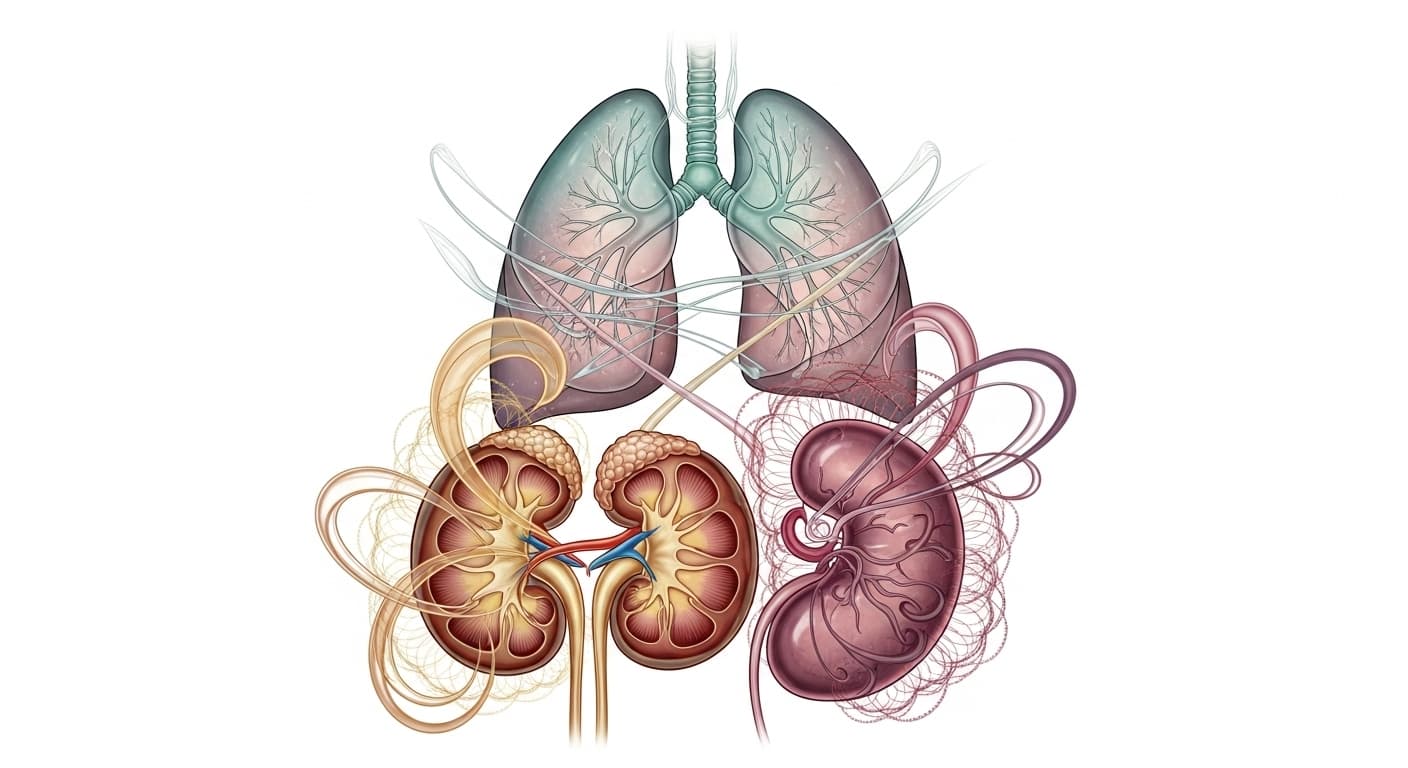

동의보감, '숨 쉬는 고통'을 말하다: 폐, 신, 비의 섬세한 균형

夫咳者 肺之病也 喘者 腎之病也 兼喘而咳者 脾肺腎皆病也

무릇 해수(咳)는 폐의 병이요, 천(喘)은 신의 병이며, 해수와 천이 겸한 것은 비장, 폐, 신장이 모두 병든 것이다.